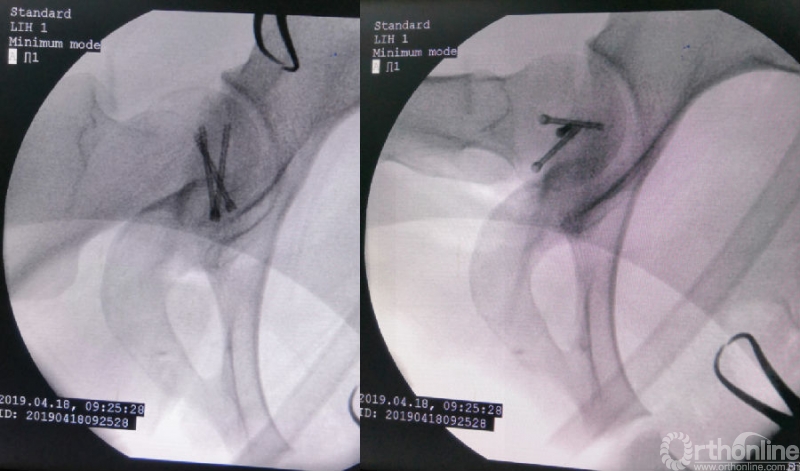

术中资料

对横跨切口远端的旋股内侧动脉血管束应特别注意,其自股骨颈的前方经内侧绕至后方延伸为旋股内侧动脉深支,是股骨头血供的主要来源。